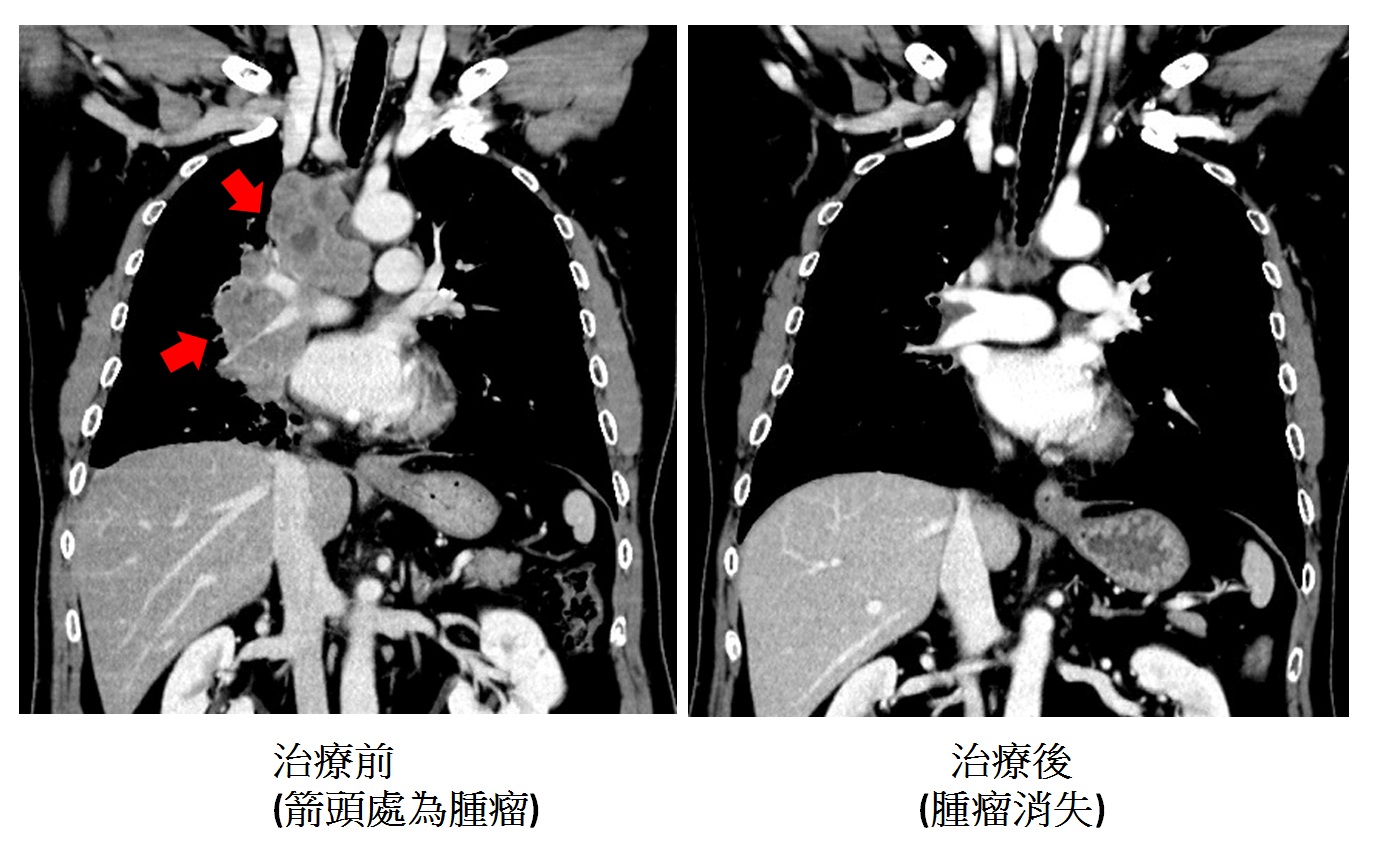

圖:腫瘤治療前後對照圖/澄清醫院提供。

劉旭崇醫師說,該患者配合接受此合併治療,一兩個療程後,其臨床症狀與影像學檢查均改善很多,他在化學治療療程結束後亦繼續接受免疫治療,現已持續超過一年半,後續追蹤發現肺腫瘤幾乎全消失,連轉移腦部與骨頭的腫瘤也消失,達到臨床上完全緩解的狀態。他目前活得很有信心且症狀改善很多,顛覆了「小細胞肺癌」患者活不久的傳統印象。劉旭崇醫師指出,免疫治療合併化療為小細胞肺癌患者提供新的選擇與希望。